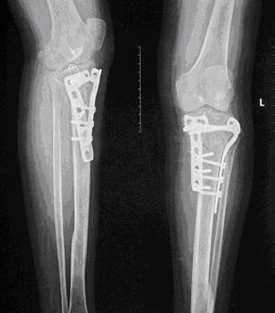

为了防止对胫骨平台骨折手术后延迟负重导致的骨折延迟愈合、关节僵直、肌肉萎缩、骨质疏松等并发症。我们在临床应用气压减重训练仪,采取早期个性化定量的减重负重训练治疗累及关节面的胫骨平台骨折。通过治疗取得良好疗效,患者的骨折愈合良好而没有出现关节面的塌陷,关节功能恢复正常(图1-3)。

图1.一例左膝胫骨平台骨折 图2.内固定术后的X线片表现